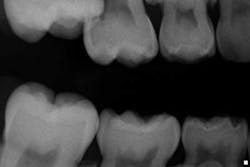

Case report A healthy 7-year-old female presents for a routine examination and cleaning (she had not been seen for two years). Crowding was noted primarily in the mandibular arch; the maxilla had a high palate. A significant amount of plaque/debris was noted in the upper right area between partially erupted No. 3 and tooth A. A bitewing radiograph on the right side barely revealed an ectopic eruption of tooth No. 3. (Fig. 1)Fig. 1Periapical and panoramic radiographs were taken and exposed a 50% resorption of the distal root and pulp chamber of tooth A. (Figs. 2 and 3)